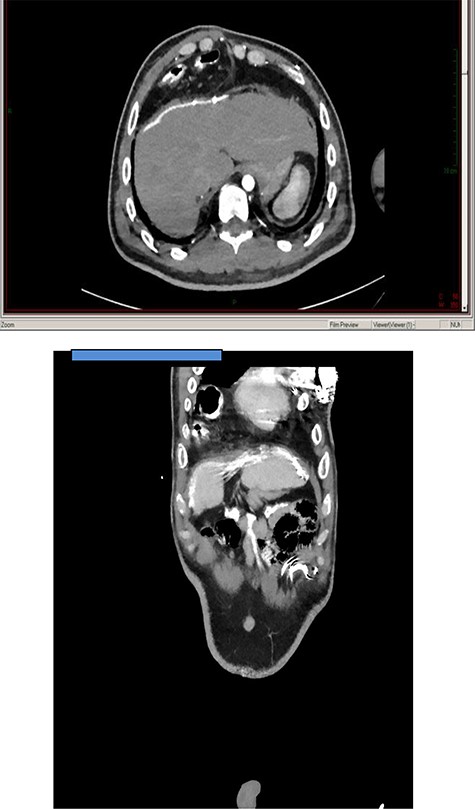

A 31-year-old male with Down’s syndrome presented with repeated hospital admissions over the previous year complaining of upper abdominal pain, nausea, postprandial vomiting and 10 kg weight loss. In 2004, he had undergone a previous laparoscopic repair of a Morgagni hernia with mesh insertion at our institution but was lost to follow-up. Past medical history included a Ventricular septal defect (VSD) repair, Atrioventricular (AV) block with pacemaker insertion and hypothyroidism. A chest X-ray (Fig. 1) showed right middle lobe consolidation, and a thoracoabdominal CT demonstrated the mesh located in the anterior thorax, which contained colon without any features of ischemia (Fig. 2). Gastroscopy and colonoscopy were normal.

Axial and coronal thoracoabdominal CT showing transthoracic displacement of a segment of colon covered by the old mesh implant.